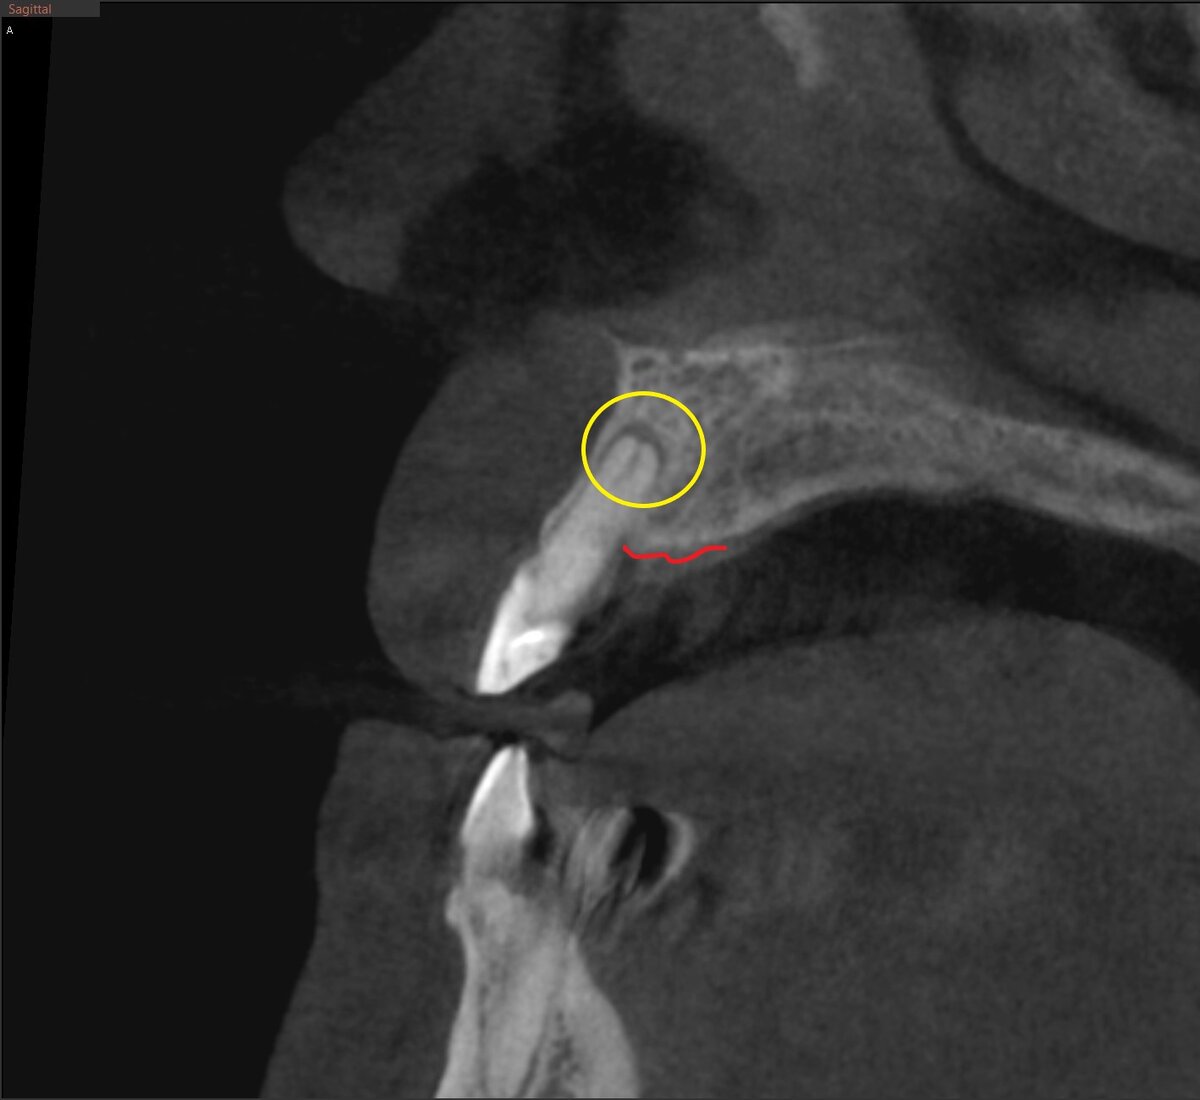

Посмотрим срезы КЛКТ.

Листайте - там все 6 зубов (один выложу аж 2 раза - для пущей убедительности).

А вот срезы КЛКТ с установленными имплантатами - листайте. По 2 среза на каждую позицию - вид спереди и вид сбоку. Потом кое-где, кое что докрутили. Чуточку самую.